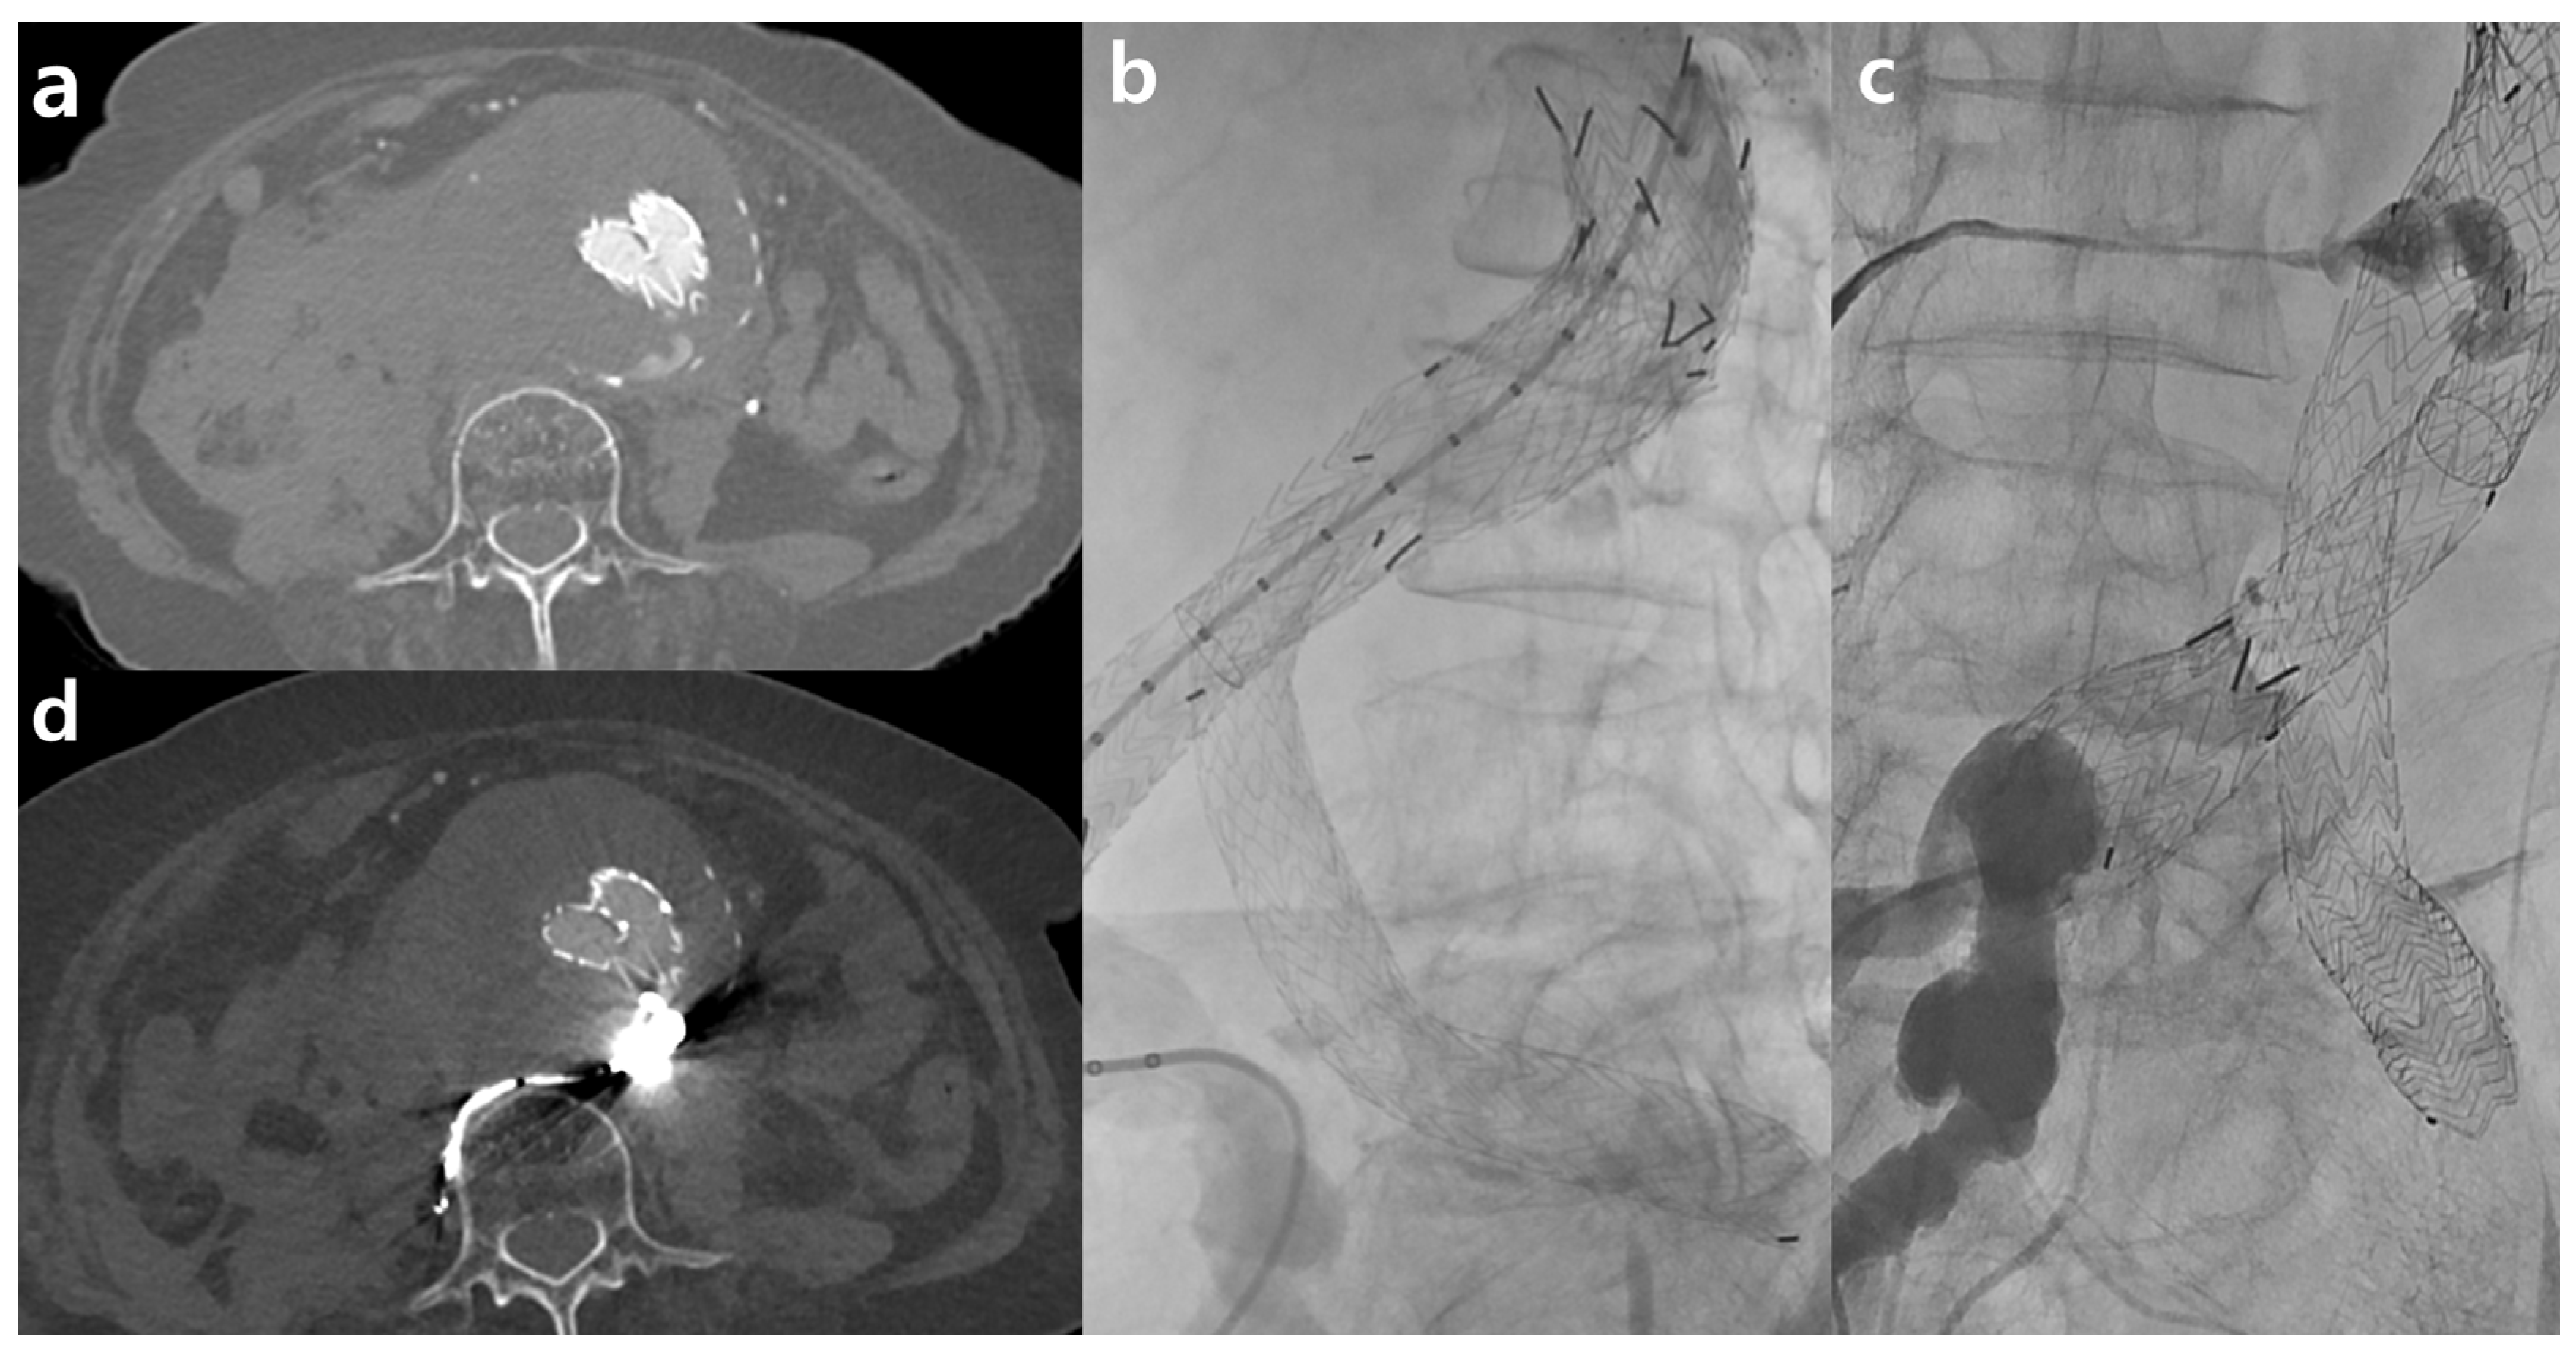

The demographic characteristics of the study population and radiation dose estimates are presented in Table 2. There were no significant differences between the two cohorts in terms of age (p = 0.583), sex (p = 1.000), or BMI (p = 0.857). However, the CT findings for TACTA varied significantly between the groups (p = 0.001). Notably, there were various findings, such as aortic aneurysms, acute aortic syndromes, and cases requiring postoperative follow-up after aortic surgery, which necessitated the scans. In the TF100kV group, two cases following EVAR procedures exhibited endoleaks, and two cases necessitated emergency TEVAR due to thoracic aorta dissection (Figure 2).

The pivotal findings of our retrospective study highlight that using Sn 100 kVP is comparable to standard protocols in diagnosing aortic or arterial diseases and preoperative planning. This comparability considers objective parameters, dose exposure, and clinical implications. In our cohort, 40% of patients undergoing either endovascular or surgical repair for acute aortic syndrome encountered no challenges in postoperative assessments, such as detecting endoleaks, even when TACTA with a TF was used. Prior studies also confirm the efficacy of TF in reducing metal artifacts without degrading image quality or increasing the dose [18]. These benefits are particularly significant in postoperative vascular lesion assessments, even in the presence of stents or stent grafts (Figure 3).

Figure 3.

Examples of third-generation dual-source computed tomography clinical applications include Sn100 spectral shaping in a patient with a type II endoleak following endovascular aneurysm repair (EVAR). After EVAR for an abdominal aorta aneurysm, there appeared to be contrast media leakage inside the aneurysm sac, suggesting an endoleak (a). The patient was suspected to have an accompanying aneurysmal sac rupture and thus underwent embolization. During aortography, contrast leakage was observed in the delayed phase (b). This seemed to originate from the right iliolumbar artery, and embolization was performed using Onyx after selection (c). A follow-up was conducted two days later using the Sn100kV protocol, where the radiopaque Onyx was visible, and no further contrast media leakage was observed (d).